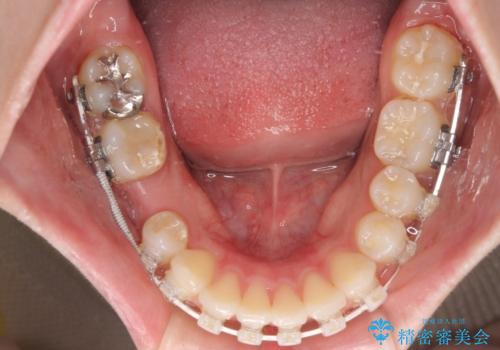

欠損した歯と前に飛び出した前歯 インプラント治療を併用したワイヤー矯正治療

- 上の前歯が下唇に当たる感覚と奥歯の欠損を気にして来院された患者様です。

上顎前歯の突出感は、上顎全体が前方に位置していることが原因であったため、補助装置により上顎全体を後方に移動させることとしました。

後方移動と同時上下歯列をワイヤー装置にて整え、奥歯の欠損部には矯正治療の途中でインプランを埋入していくこととしました。